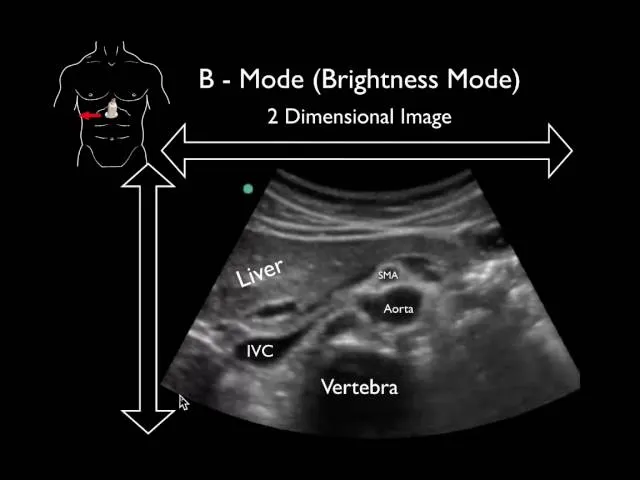

- B-Mode (Brightness): 2D grayscale. Echo strength as dot brightness. Foundation of US imaging.

⭐ B-mode (Brightness mode) forms the basis of most ultrasound examinations, creating 2D anatomical images that are fundamental for diagnosis across various medical specialties.